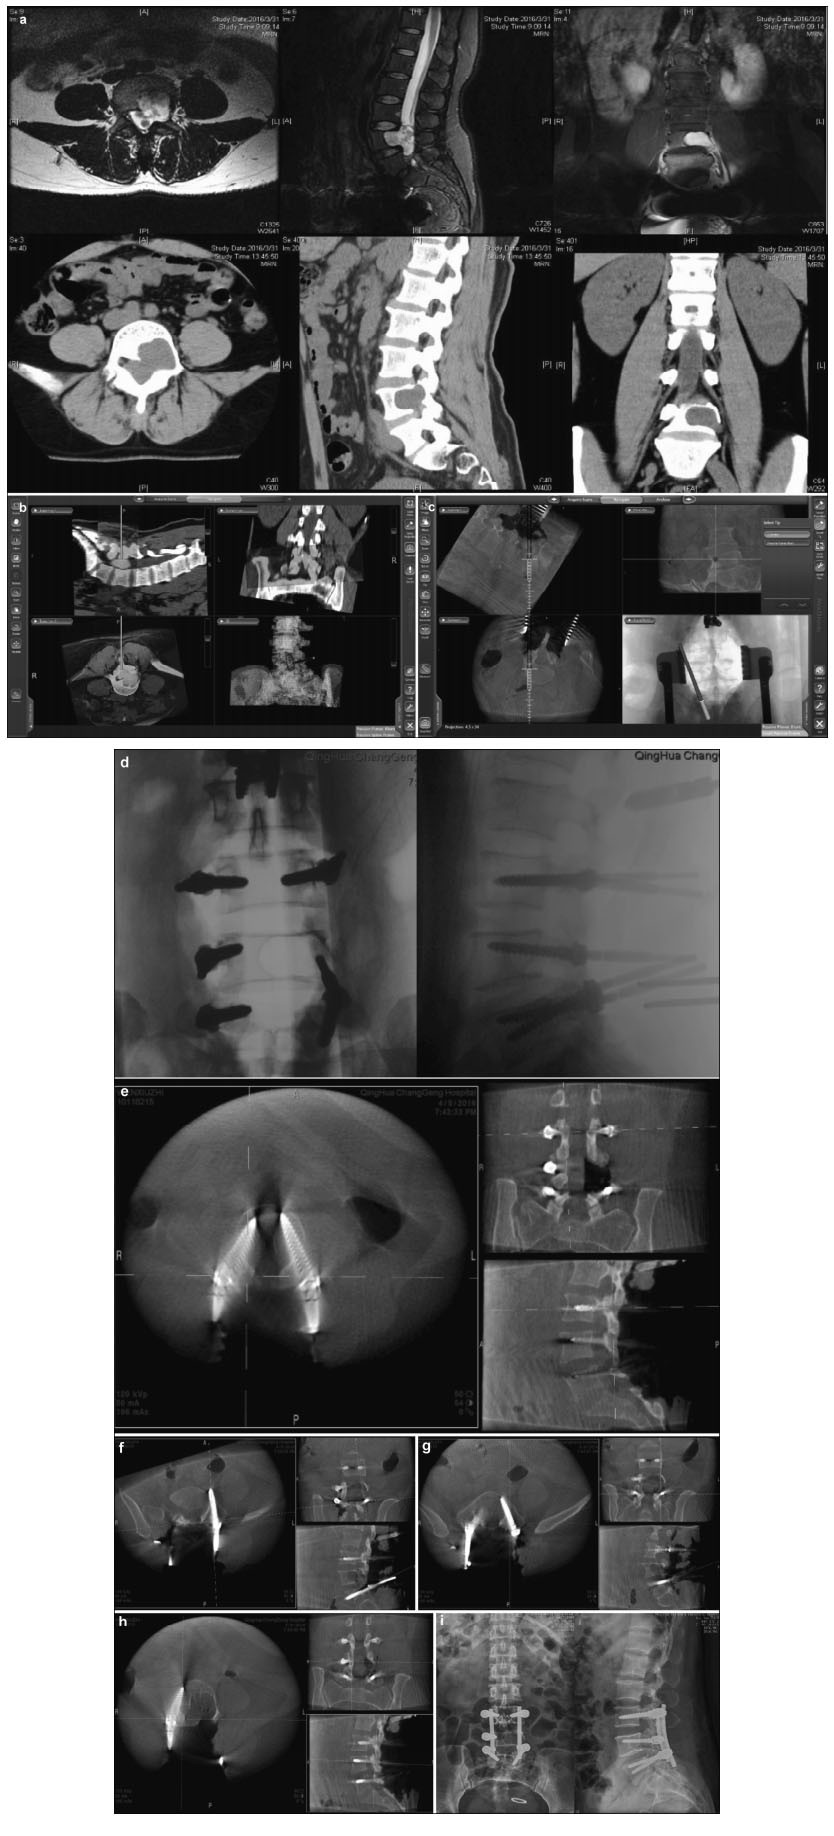

3.1 Pedicle screw position accuracyIn the occipitocervical fusion group, a total of 182 cervical screws were implanted with navigation assistance, including 64 C2 Pars screws and 118 C3 and/or C4 lateral block screws. Intraoperative O-arm 3D scans revealed 176 Richter grade Ⅰ screws and 6 grade Ⅰ screws penetrating the lateral block cortex near the vertebral artery (Figure 1), yielding an accuracy of 96.7% (176/182). Among the 84 occipital screws, 3 deviated from the occipital posterior midline position, yielding an accuracy of 96.4% (81/84).

| Figure 1 Preoperative, intraoperative, and postoperative images of patients with atlantoaxial dislocation and occipitocervical fusion. Preoperative cervical radiography in the side (a), anteflexion (b), and supine (c) positions reveals odontoid instability and a backward and upward shift. Preoperative computed tomography (CT) (d) and magnetic resonance imaging (MRI) (e) show that the backward and upward dislocation of the C2 odontoid impacts the brain stem. The foramen magnum is narrow, and the cervical cord void is visible. (f) Implantation direction and C2 angle. Pars screws are planed under intraoperative navigation. (g) O-arm three-dimensional scan, after screw implantation, shows that the Pars screw to the right of C2 penetrates the bone cortex and is near the vertebral artery. Lateral radiography (h), sagittal CT (i), and a T2 sagittal scan (j), 1 week after the operation, show firm screw fixation in a good position and inferoanterior displacement of the odontoid to the C1 level, essentially achieving normal anatomical reduction. Brain stem compression is released, and the posterior cranial fossa is fully decompressed. |